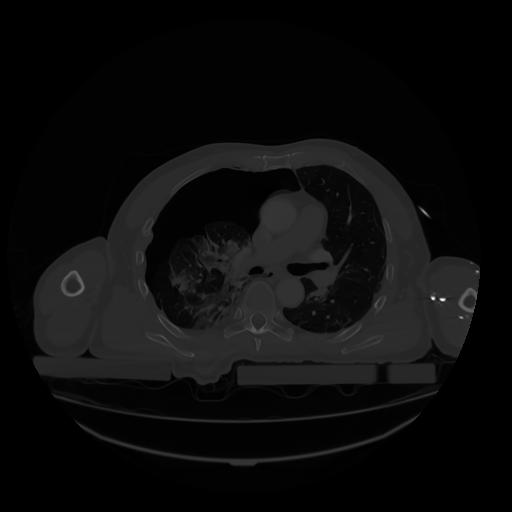

28 CUERPO,CE,Vol,2.0,CUERPO,,